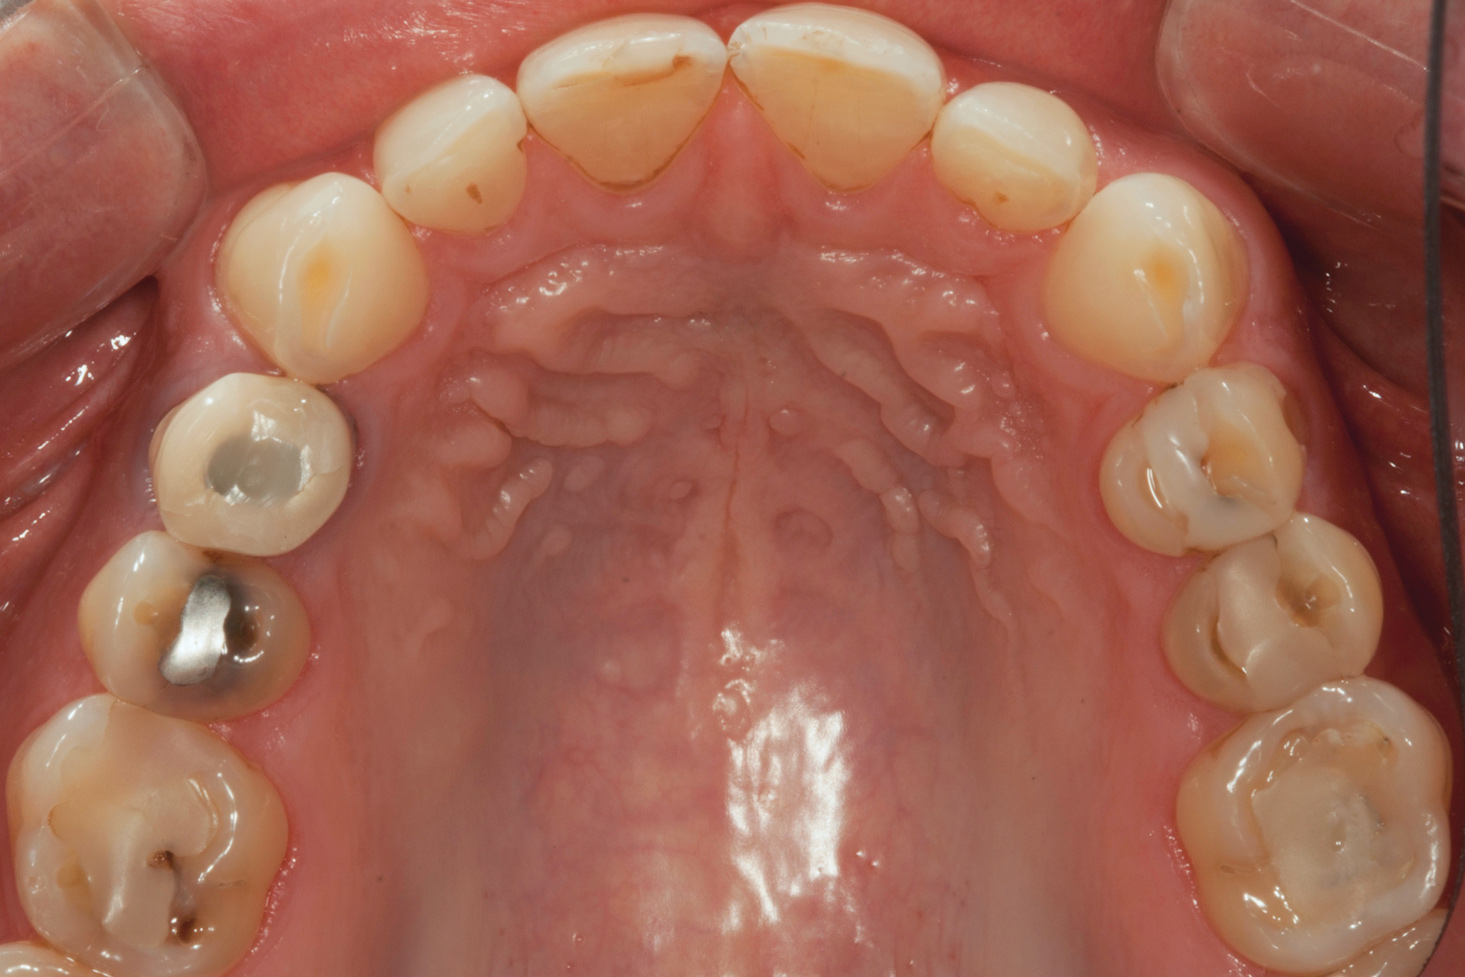

A 34-year-old male patient with no medical issues presented to the office with the chief complaint of a failing crown on tooth No. 12. The patient was also unhappy with his bite and the appearance of his teeth (Figure 1 and Figure 2).

A comprehensive examination was carried out, and preoperative photographs were taken (Figure 1 through Figure 4). The patient presented with fair oral hygiene and slight, generalized tissue inflammation. Caries and defective restorations were detected on teeth Nos. 4, 5, 13, and 14. The crown on tooth No. 12 was showing signs of leakage, and although the endodontic access cavity had been temporarily restored with composite, this endodontic re-treatment was acceptable and the tooth was otherwise symptom-free. Erosion was present on most of the posterior teeth and the cuspids, and abrasion was noted on teeth Nos. 4, 5, 10, 11, 20, 21, 22, 28, and 29. An examination of the patient's muscles, joints, and bite revealed no joint sounds, a normal range of motion, and negative joint load and immobilization tests.

The dentofacial examination revealed a low smile line with no incisor display when the lips were in repose. The anterior teeth were chipped and worn, and their overall color was darkened. The buccal corridors were deficient, and the failing crown on tooth No. 12 was visible in a full smile.

(1.) Preoperative smile photograph.

Figure 1